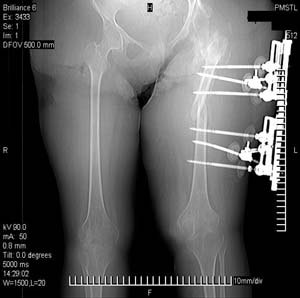

Хотелось бы увидеть рану с разных ракурсов и рентгенограммы таза и бедра. Тогда можно создать представление о площади и глубине раны.

Можно наложить простейший аппарат таз-бедро и подвесить больного (он с ним и ходить сможет), а потом спокойно перемещать лоскуты.

Такая мысль тоже приходила. Не решились, так как:1.Выраженный остеопороз костей таза и бедра, больная тучная - высок риск того, что стержни не выдержат. 2.Сейчас больная передвигается в инвалидном кресле - хоть какая-никакая, а динамизация. Если лишить её этой возможности - застойная пневмония со всеми вытекающими...